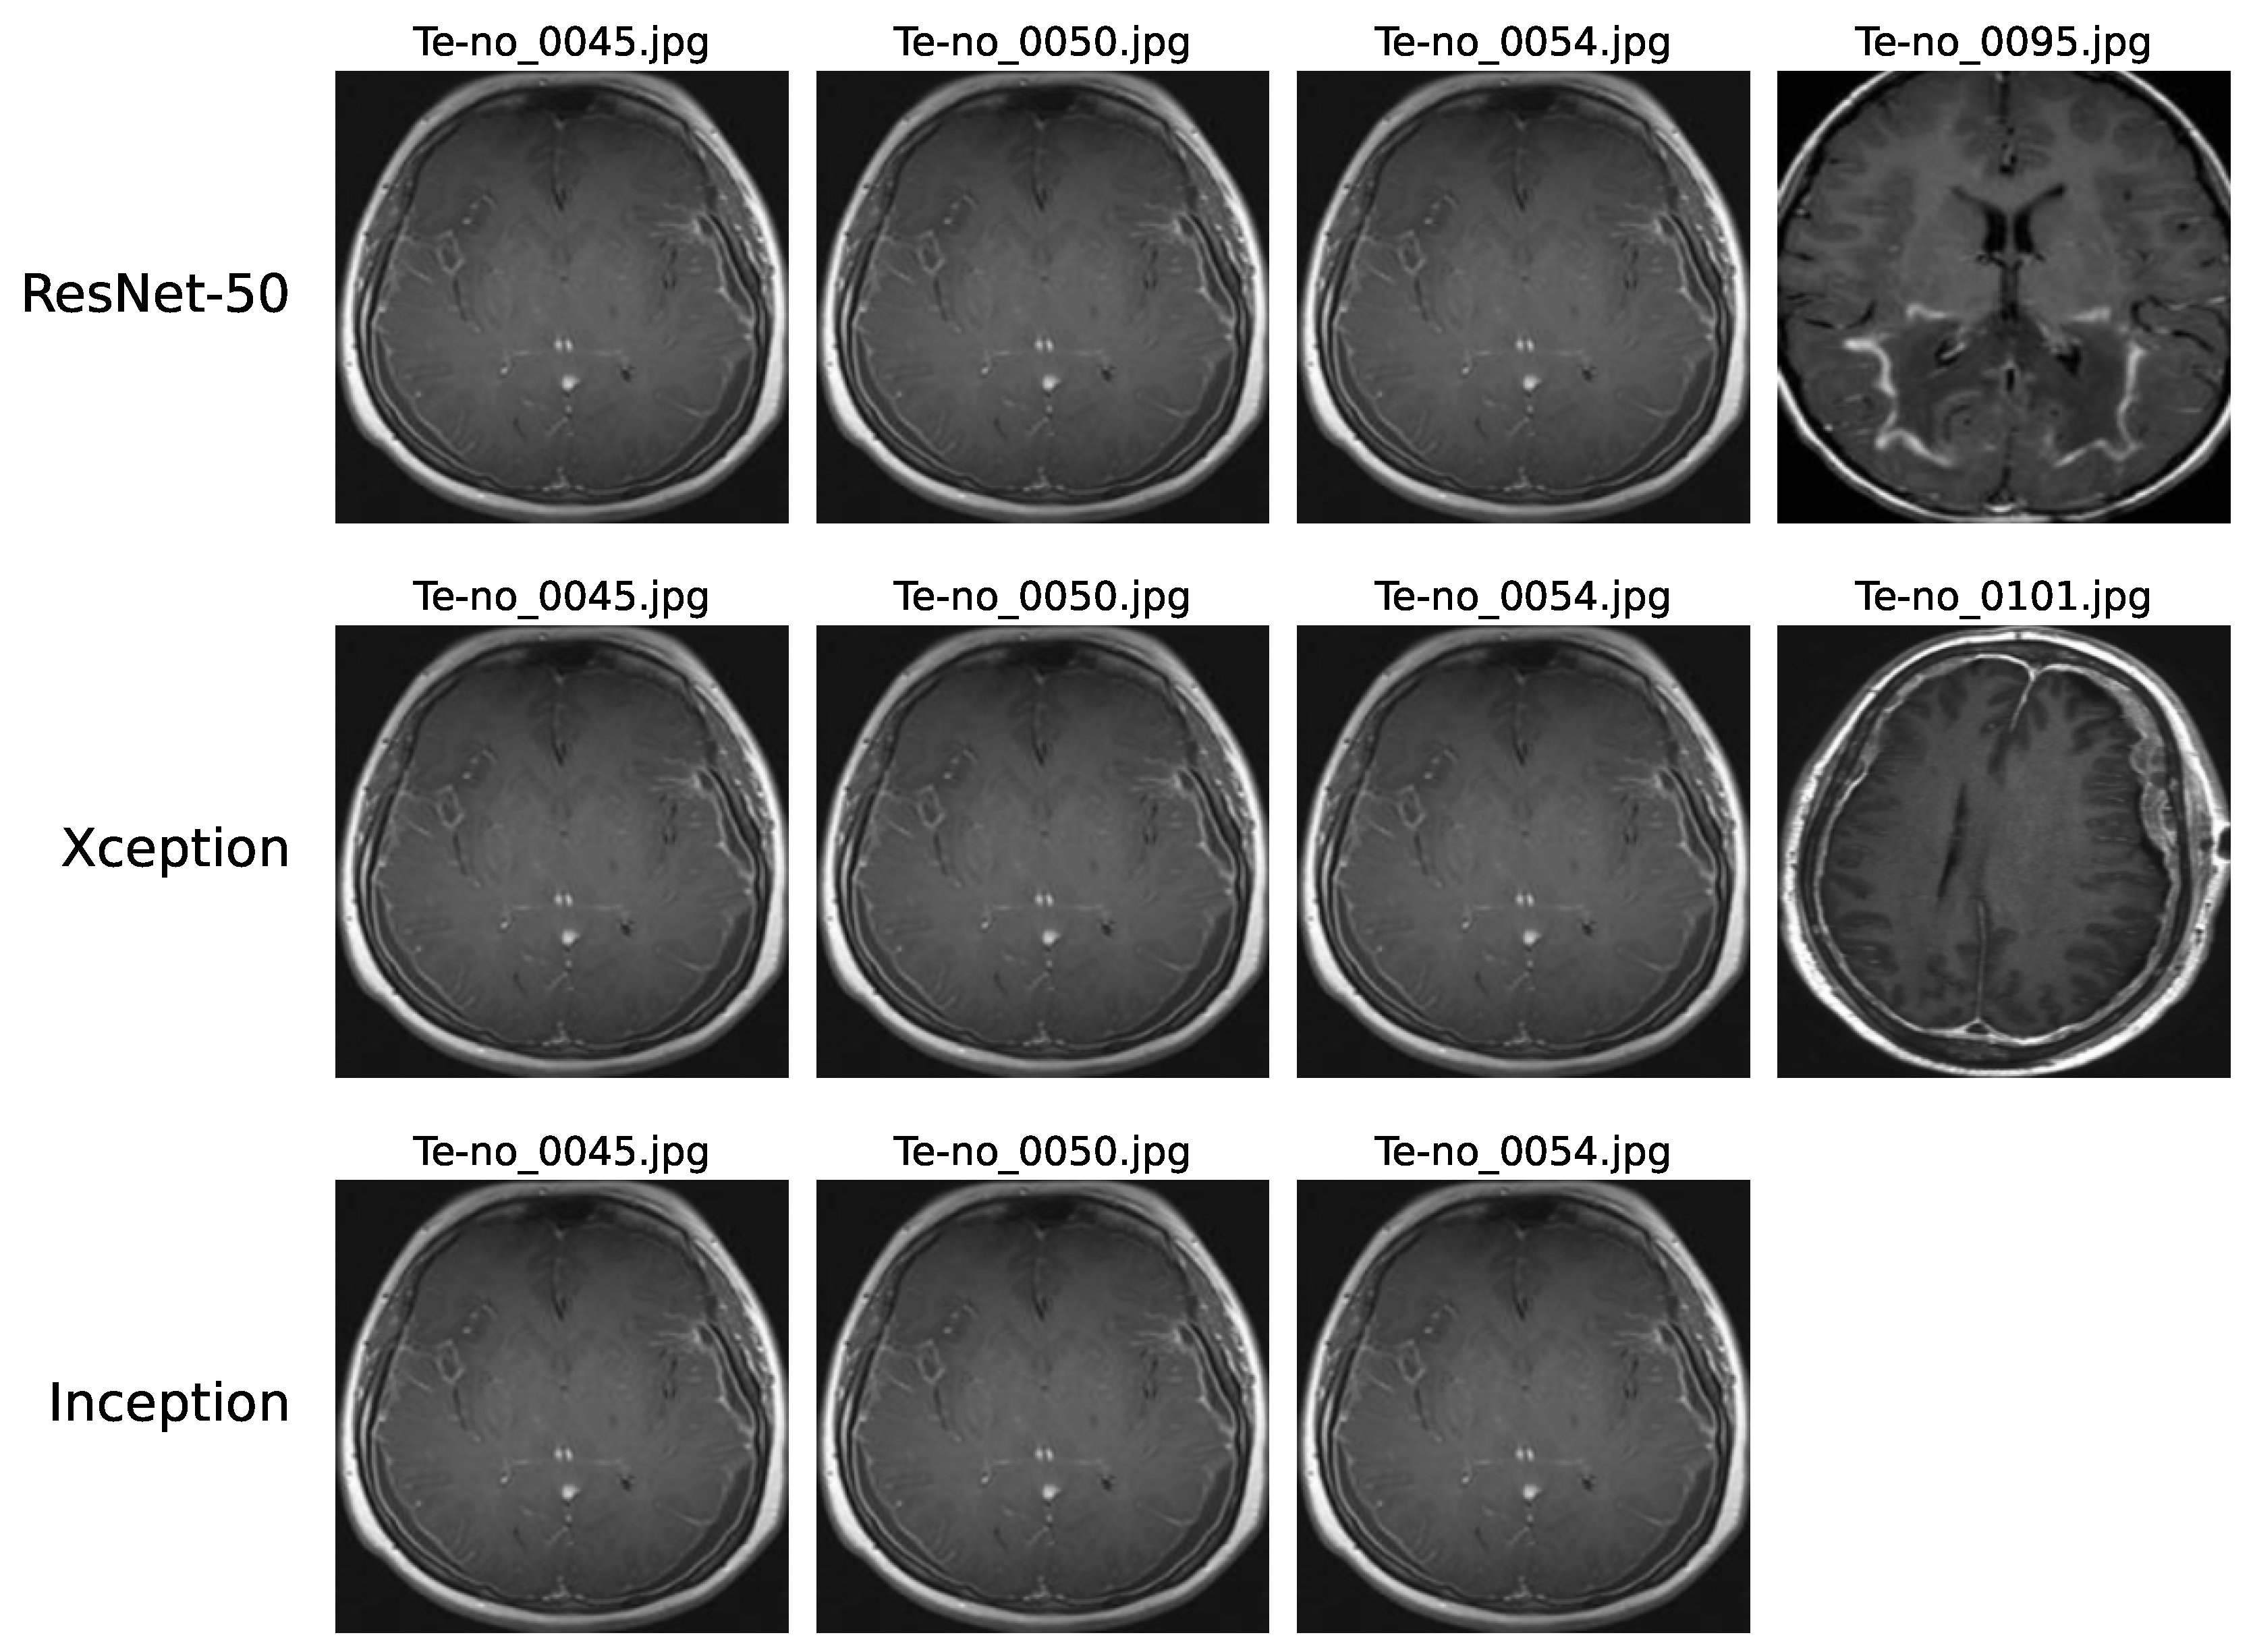

Upon examining the confusion matrices for ResNet-50, Xception, and InceptionV3, significant misclassifications were evident. Specifically, ResNet-50 inaccurately labeled 4 “No-tumor” images as “Glioma”, while Xception and InceptionV3 misclassified 4 and 3 such images, respectively. Figure 9 underscores that three “No-tumor” images were consistently misdiagnosed as “Glioma” across all models, with InceptionV3 exclusively misclassifying all “No-tumor” images as “Glioma” from these instances.

Figure 9.

Instances of no-tumor images misdiagnosed as Glioma on ResNet-50, Xception, and InceptionV3 models.

These misclassifications can be attributed to various factors. The complexity of these models may limit their ability to capture intricate patterns in MRI scans effectively. Issues like low resolution or blurry scans can impede accurate feature extraction, thereby affecting classification precision. Additionally, artifacts or noise prevalent in MRI scans might introduce confusion, challenging the models’ interpretation of image content. Furthermore, discerning early-stage Glioma from MRI scans showing no tumors, which may present minimal discernible differences, poses a notable challenge.

In Figure 10, the error analysis among ResNet-50, Xception, and InceptionV3 illustrates that each model made errors in 17, 18, and 19 images, respectively. Notably, a significant portion of Xception’s and InceptionV3’s errors originated from the same images, highlighting consistent performance trends for these two models on this dataset. This overlap in error patterns can be attributed to the fact that Xception is an evolution of the Inception architecture. Xception builds upon the Inception framework by incorporating depthwise separable convolutions, which maintain a high degree of structural similarity with InceptionV3. Consequently, the similarity in model construction explains why both architectures exhibit comparable error patterns on the same images. Furthermore, six images were misclassified by all three models, emphasizing common challenges across different model architectures. Further in-depth analysis is crucial to pinpoint specific reasons behind these misdiagnoses, offering deeper insights and enabling effective mitigation of underlying issues. Such meticulous examination is pivotal for enhancing the accuracy of model predictions in intricate tasks like multi-class brain tumor classification.